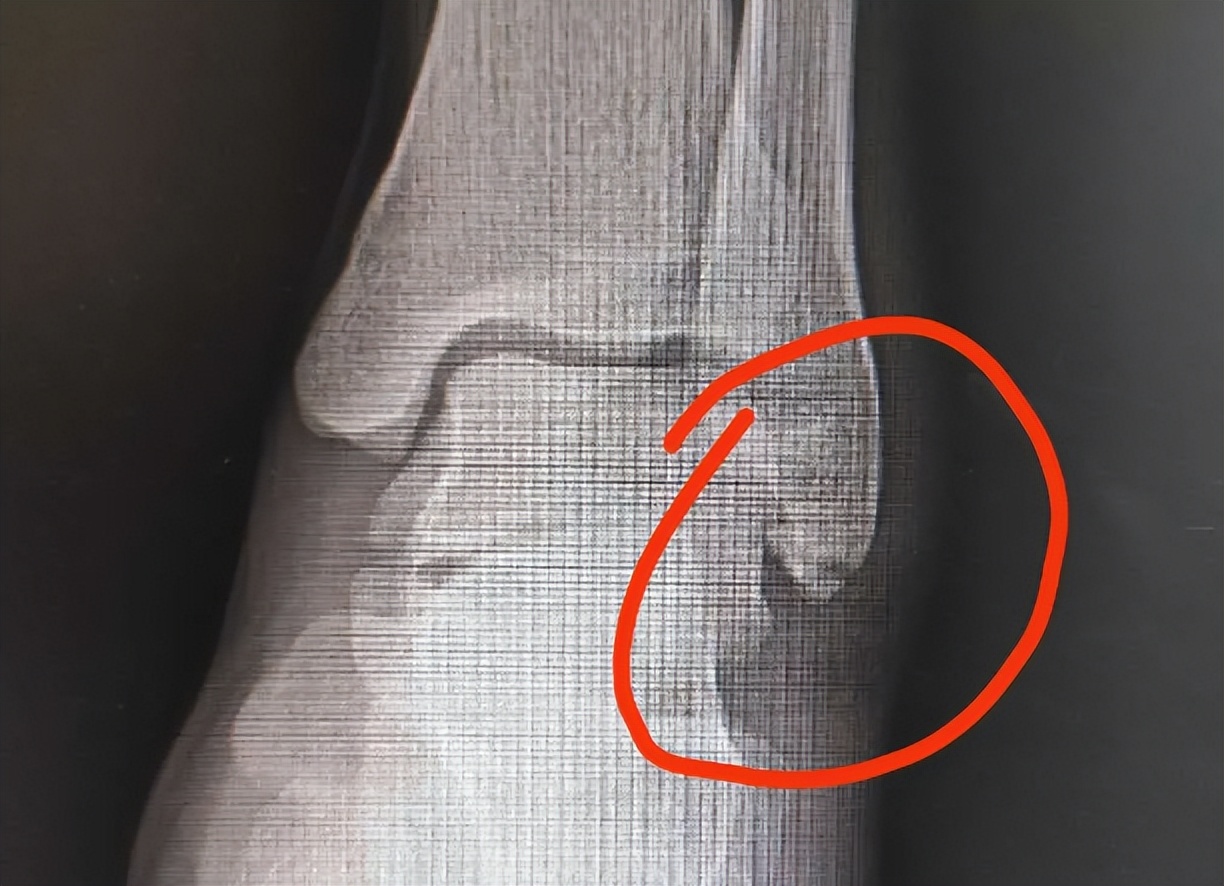

检查后发现,小王的右髂(qià)部有些肿胀,右髋的屈伸活动部分受限,此时距受伤已经过去六七个小时,但小王仍痛感强烈,这显然不是普通扭伤,进行骨盆CT检查后,检查结果却让小王惊出一身冷汗——骨盆撕脱性骨折。他怎么也想不通:只是“扭”了一下,怎么会骨折?专家来为你作出详细解答。

撕脱性骨折是骨折的一种,人在剧烈活动中的肌肉收缩,随着韧带牵拉造成韧带附着处骨质随韧带一起剥离下来,形成碎骨片,这称为撕脱性骨折。通俗点说就是肌肉肌腱拉力过大, 在外力的作用下,导致附着的骨头发生骨折,撕裂下整块或者一小部分的骨质残片。

朱泽兴表示,不同年龄段的人群在运动过程中发生撕脱性骨折的部位不同。 尤其青少年, 他们的韧带强度比骨头要结实,所以在练习短跑或跨栏等运动时,由于剧烈的运动,韧带容易把髋部的骨头拉掉。而成年人的骨头比韧带结实,但因为踝关节支撑了人体大部分的重量,所以踝关节周围的韧带比较结实,有些人会因为扭伤等意外出现踝关节撕脱性骨折。